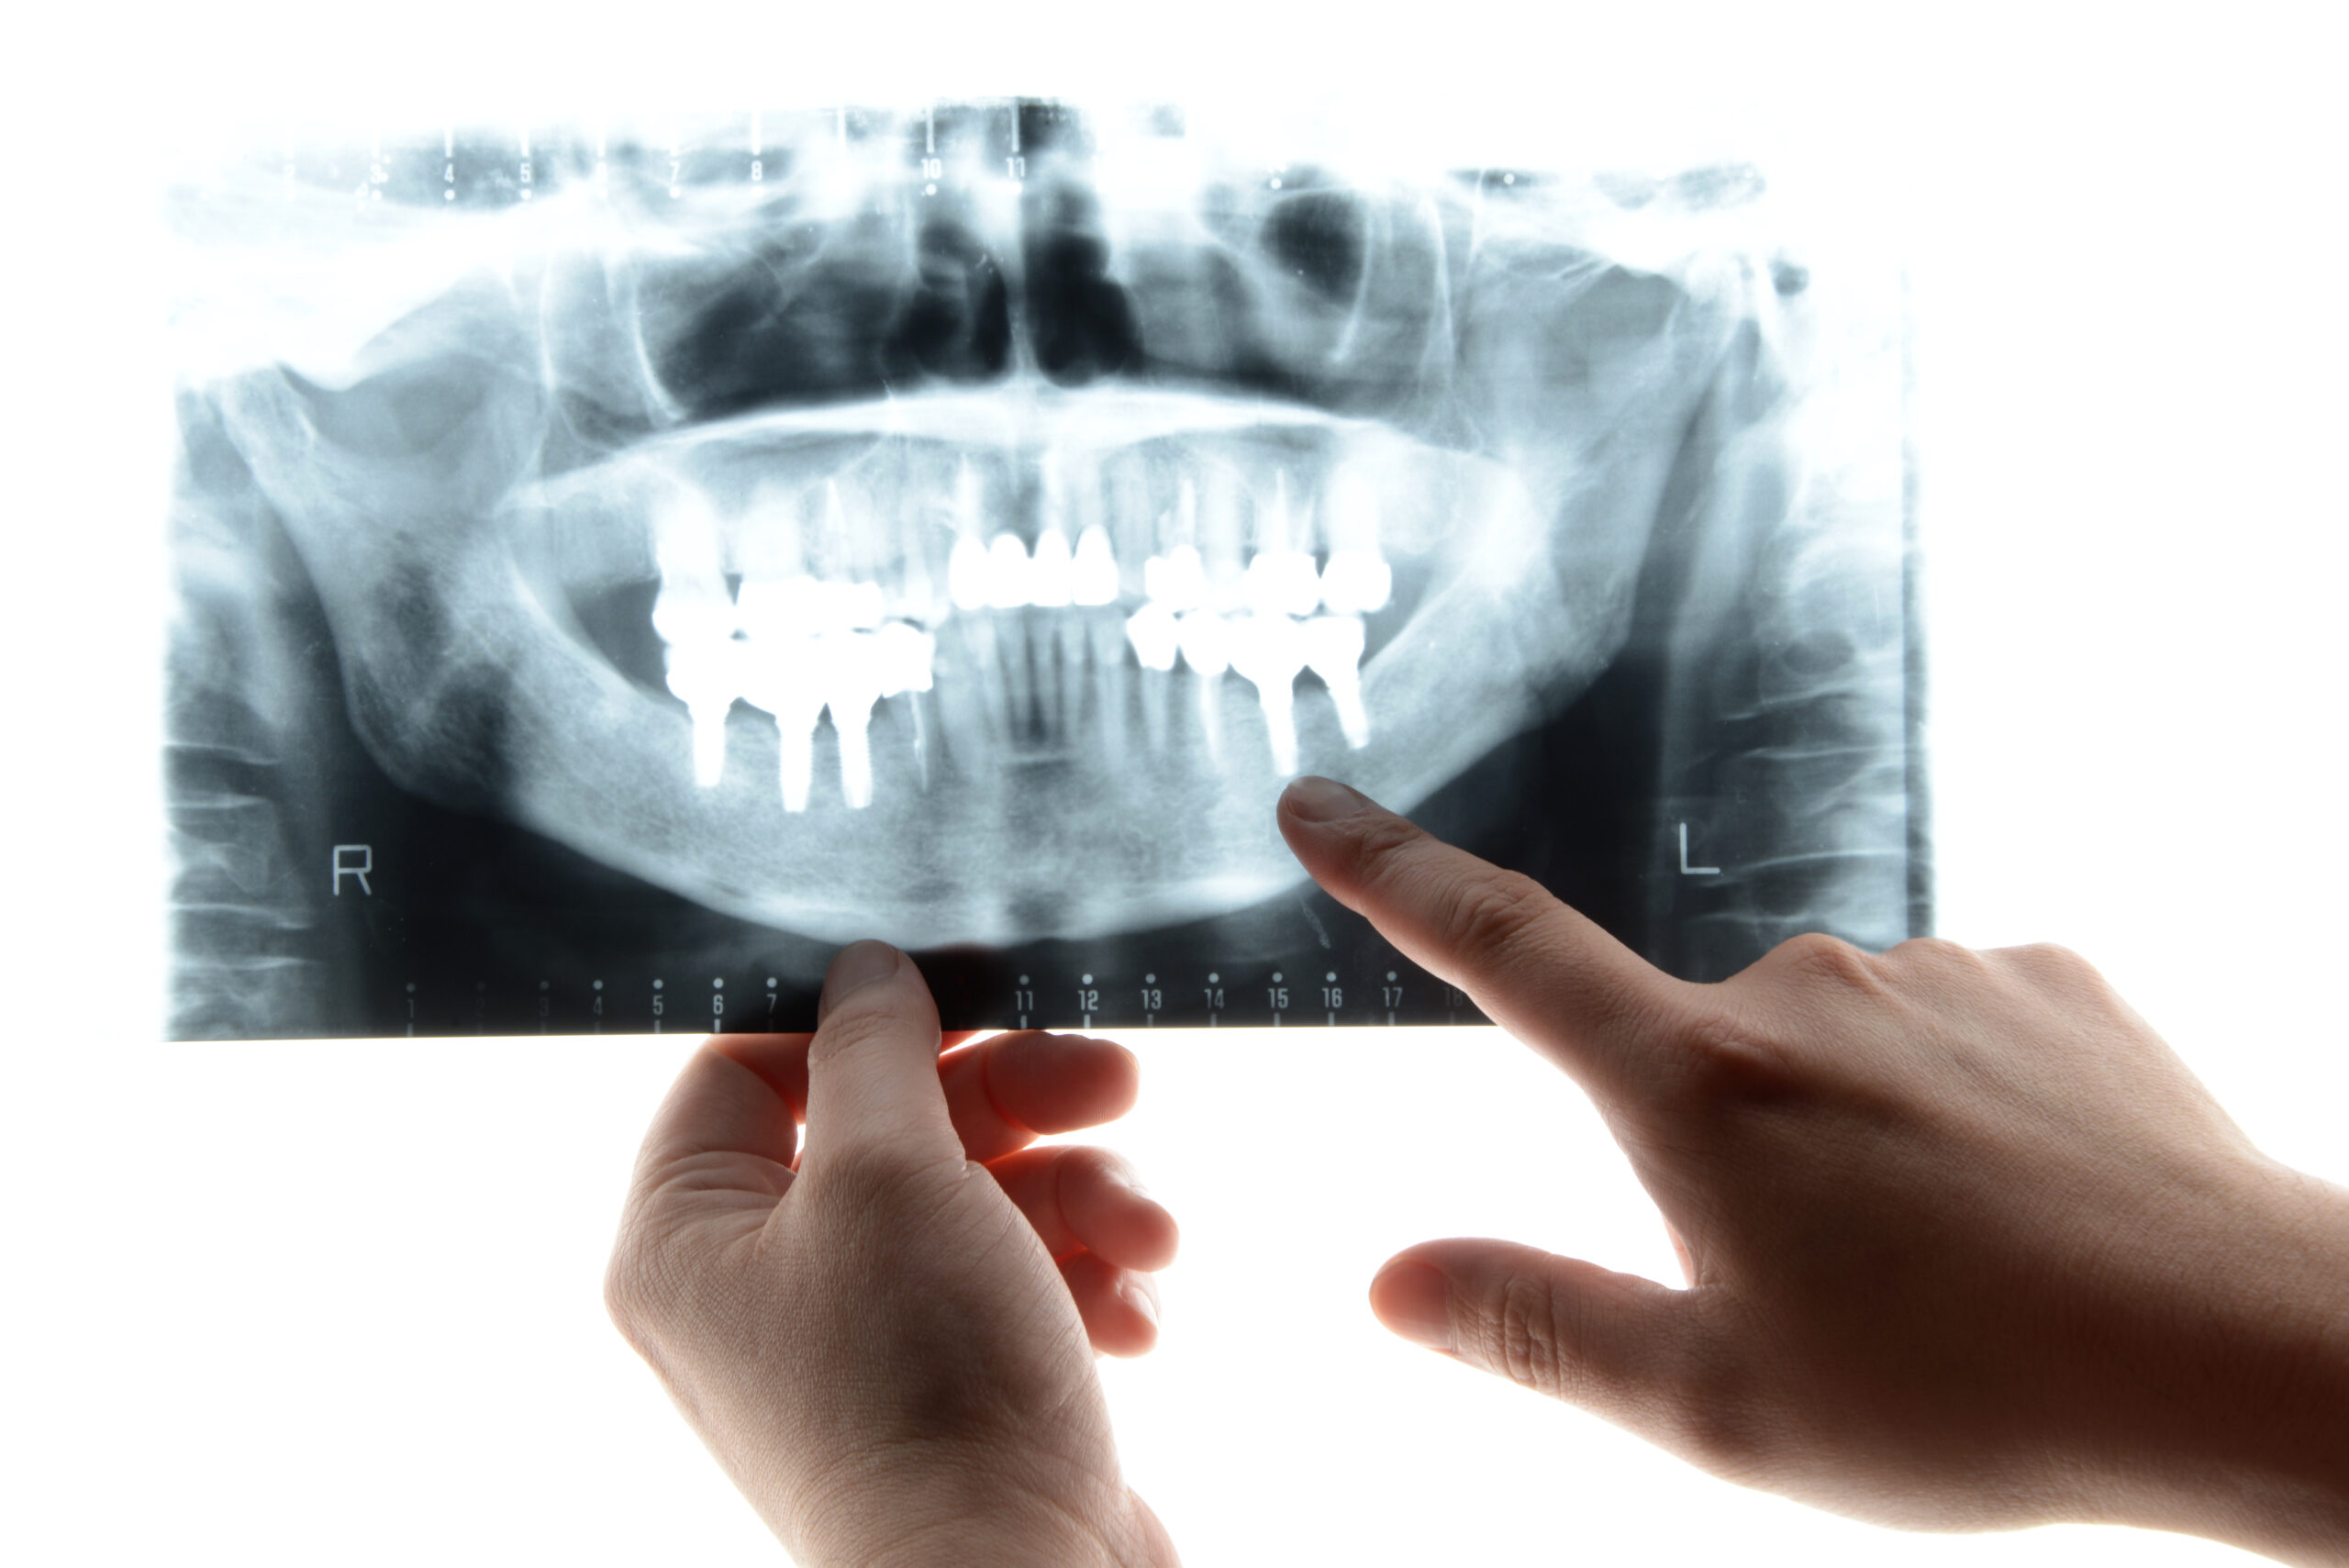

CTを駆使した詳細な診断

遠藤歯科クリニックでは歯科用CTを完備しており、症例ごとに骨の状態を詳細に把握し治療に活かしています。通常のレントゲンではわからないこともCTの3次元画像では手に取るように把握でき、手術の際に非常に有用です。安心安全な手術のためにもCT撮影は必須と考えています。インプラント治療を行う場合は全症例でこのCT撮影をさせていただいております。